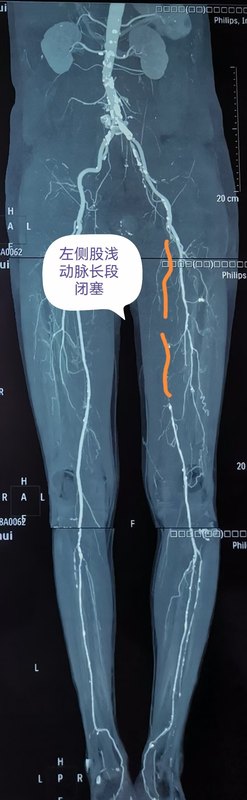

哈醫(yī)大四院血管外科完成省內(nèi)首例準(zhǔn)分子激光消蝕減容術(shù)治療下肢動(dòng)脈硬化閉塞癥

聽說過激光能祛斑、祛疤、治近視眼,您聽說過激光還可以通血管么?日前,哈醫(yī)大四院血管外科應(yīng)用準(zhǔn)分子激光設(shè)備,率先在省內(nèi)成功為一位高齡下肢動(dòng)脈硬化閉塞癥患者開通閉塞血管,完成我省首例應(yīng)用準(zhǔn)分子激光消蝕減容術(shù)治療下肢動(dòng)脈硬化閉塞癥的手術(shù)。謝大娘今年80歲,半年前自覺右下肢疼痛,麻木,皮溫涼,跛行距離100米,未進(jìn)行治療。半月前疼痛加重,出現(xiàn)患足靜息痛,跛行距離僅為10米,且夜間疼痛明顯加重,嚴(yán)重影響生活質(zhì)量。家屬帶謝大娘來到哈醫(yī)大四院血管外科,黃任平主任接診后通過下肢動(dòng)脈CTA發(fā)現(xiàn)患者右側(cè)股總動(dòng)脈、股淺動(dòng)脈閉塞,考慮患者癥狀明顯,如不進(jìn)行手術(shù)干預(yù),缺血加重可能會(huì)導(dǎo)致肢體壞疽,截肢可能。經(jīng)過縝密的術(shù)前討論,黃任平主任決定采用我院剛剛引進(jìn)的準(zhǔn)分子激光設(shè)備為患者開通病變血管。黃任平主任團(tuán)隊(duì)為患者實(shí)施手術(shù),通過左側(cè)股動(dòng)脈穿刺翻山至右側(cè),導(dǎo)入準(zhǔn)分子激光導(dǎo)管,對閉塞動(dòng)脈血管進(jìn)行消融,消融后即刻可見血管恢復(fù)通暢。然后導(dǎo)入藥物涂層球囊擴(kuò)張,再次血管造影可見股腘動(dòng)脈通暢,血液流速快,術(shù)后患者足背及脛后動(dòng)脈搏動(dòng)恢復(fù),右下肢靜息痛消失,跛行癥狀明顯緩解,目前患者已經(jīng)康復(fù)出院。黃任平主任介紹,準(zhǔn)分子激光消蝕術(shù)(ExcimerLaserAtherectomy,ELA)是一種在歐美國家常規(guī)使用的冠脈介入治療手段,應(yīng)用準(zhǔn)分子激光治療下肢動(dòng)脈硬化閉塞癥在國外已經(jīng)開展多年,在我國開展較晚,該手術(shù)在我省尚屬首例。其原理是在光化學(xué)作用下,斑塊組織對308nm激光能量的吸收可引起分子鍵的斷裂,碎化成直徑小于25um的碎片,因此該準(zhǔn)分子激光可以安全消蝕溶解血管內(nèi)的血栓、斑塊等組織,更有效的開通閉塞的血管,同時(shí)能夠保證開通血管的遠(yuǎn)期通暢率,減少了支架的植入。該技術(shù)適合在下肢動(dòng)脈硬化閉塞癥,血栓閉塞性脈管炎,以及支架再閉塞等嚴(yán)重下肢缺血患者治療中應(yīng)用。?????????????專家簡介??????????????????????黃任平醫(yī)學(xué)博士、博士后,碩士生導(dǎo)師哈爾濱醫(yī)科大學(xué)附屬第四醫(yī)院血管外科主任???專業(yè)方向:擅長血管外科的常見病多發(fā)病的診治,從事微創(chuàng)血管病治療與創(chuàng)面治療10余年,治愈各種靜脈曲張、糖尿病足、下肢靜脈血栓、脈管炎、動(dòng)脈硬化閉塞癥、胸腹主動(dòng)脈瘤、動(dòng)脈栓塞、肺栓塞、鎖骨下動(dòng)脈閉塞、腎動(dòng)脈狹窄、嬰幼兒血管瘤、血管畸形等20000余例。出診地點(diǎn):哈爾濱醫(yī)科大學(xué)附屬第四醫(yī)院門診三樓C區(qū)外科3診室咨詢電話:0451-82576869